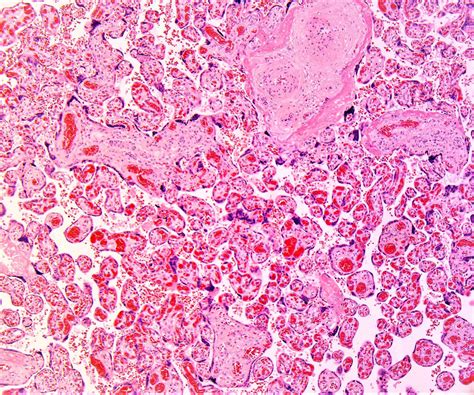

Structural Changes

Research has shown that the placenta in COVID-19-positive mothers may exhibit structural abnormalities. These changes can include:

• Increased inflammation and immune cell infiltration.

• Thrombosis (blood clots) in the placental vessels.

• Intervillous thrombosis, which can impair blood flow to the fetus.

• Fetal vascular malperfusion, leading to reduced nutrient and oxygen supply.

These structural changes can compromise the placenta's ability to support fetal growth and development, potentially leading to adverse pregnancy outcomes.